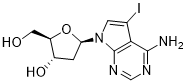

馬鞍山致研生物醫(yī)藥科技有限公司成立于馬鞍山市鄭浦港新區(qū)現(xiàn)代產(chǎn)業(yè)園。公司專(zhuān)注于生物小分子、醫(yī)藥中間體相關(guān)產(chǎn)品的研發(fā)和生產(chǎn),產(chǎn)品主要包括DNA亞磷酰胺單體、RNA亞磷酰胺單體、特殊單體以及按照客戶(hù)要求定制的RNA和DNA,并且公司提供定制合成等方面的研究服...

馬鞍山致研生物醫(yī)藥科技有限公司成立于馬鞍山市鄭浦港新區(qū)現(xiàn)代產(chǎn)業(yè)園。公司專(zhuān)注于生物小分子、醫(yī)藥中間體相關(guān)產(chǎn)品的研發(fā)和生產(chǎn),產(chǎn)品主要包括DNA亞磷酰胺單體、RNA亞磷酰胺單體、特殊單體以及按照客戶(hù)要求定制的RNA和DNA,并且公司提供定制合成等方面的研究服...